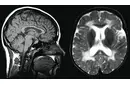

Bu belirtiler, kistin beyin üzerindeki etkilerine bağlı olarak değişiklik gösterebilir. Dolayısıyla, ebeveynlerin bebeklerinde bu tür belirtiler gözlemlemesi durumunda hızlı bir tıbbi yardım alması önemlidir. Bebeklerde Beyin Kistlerinin Tanısı Bebeklerde beyin kistlerinin tanısı genellikle aşağıdaki yöntemlerle yapılır:

Bu tanı süreçleri, doktorun kistin doğasını anlamasına ve uygun tedavi yöntemini belirlemesine yardımcı olur. Bebeklerde Beyin Kistlerinin Tedavisi Bebeklerde beyin kistlerinin tedavisi, kistin türüne, boyutuna ve bebeğin genel sağlık durumuna bağlı olarak değişiklik göstermektedir. Tedavi seçenekleri şunlardır:

19 haftalik hamileyim bebegimin beyninde iki tarafli kirst var dedi doktor.çok korkuyorum. Baska doktora gittim o hiçbirşey yok dedi

Anladığınız gibi, farklı doktorların farklı görüşleri olabilir. Öncelikle sakin kalmalısınız. İkinci bir doktorun hiçbir şey olmadığını söylemesi rahatlatıcı olabilir. Ancak, içinizin daha rahat etmesi için bir perinatolog veya fetal tıp uzmanına danışmanız faydalı olabilir. Bu uzmanlar, yüksek riskli gebeliklerde daha spesifik değerlendirmeler yapabilirler. Sağlıklı bir gebelik süreci geçirmenizi dilerim.

22 haftalik hamileyim bebeğinin kafasında küçük bir kist olduğunu söyledi neden kynklnoyo acaba